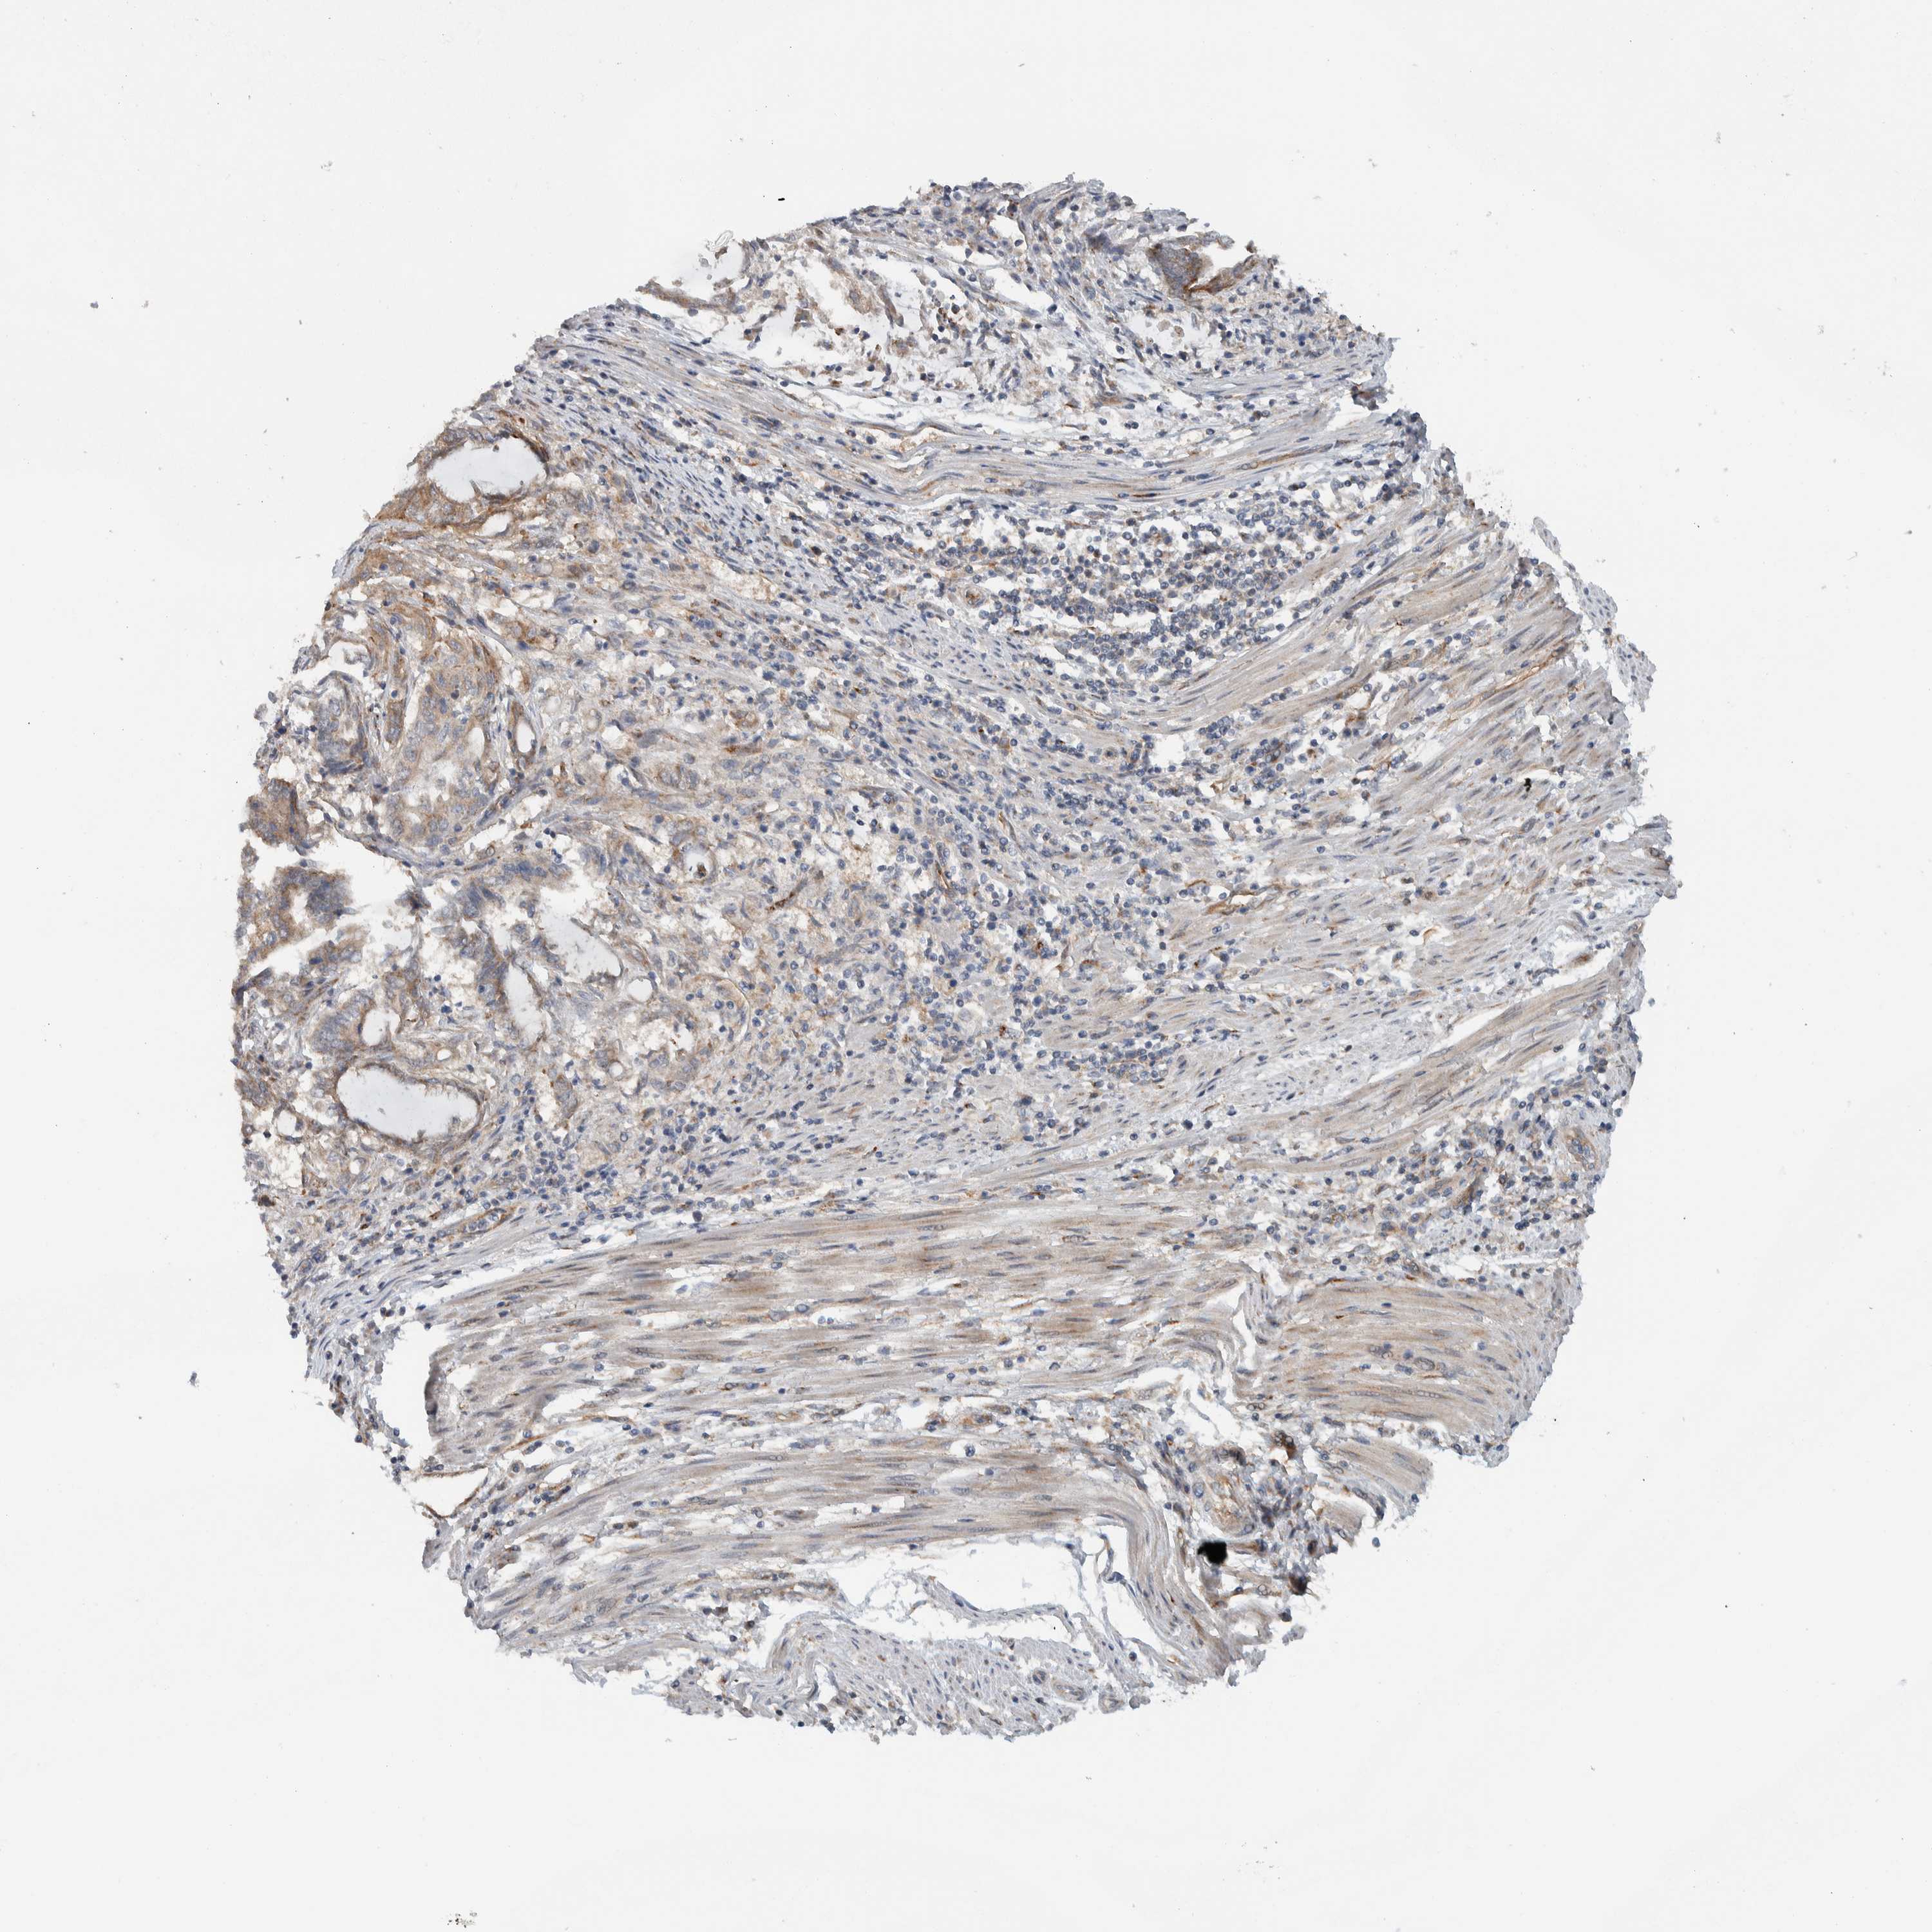

ENDOMETRIAL CANCER - Protein expressioni

A mouse-over function shows sample information and annotation data. Click on an image to view it in a full screen mode. Samples can be filtered based on level of antibody staining by selecting one or several of the following categories: high, medium, low and not detected. The assay and annotation is described here.

Note that samples used for immunohistochemistry by the Human Protein Atlas do not correspond to samples in the TCGA dataset.

Antibody stainingi

Antibody staining in the annotated cell types in the current human tissue is reported as not detected, low, medium, or high, based on conventional immunohistochemistry profiling in selected tissues. This score is based on the combination of the staining intensity and fraction of stained cells.

Each image is clickable and will lead to virtual microscopy that enables deeper exploration of all samples and also displays staining intensity scores, fraction scores and subcellular localization as well as patient and tissue information for each sample.

Antibody HPA024093

Staining

High

Medium

Low

Not detected

Intensity

Strong

Moderate

Weak

Negative

Quantity

>75%

75%-25%

<25%

None

Location

Nuclear

Cytoplasmic/membranous

Cytoplasmic/membranous,nuclear

Adenocarcinoma, NOS